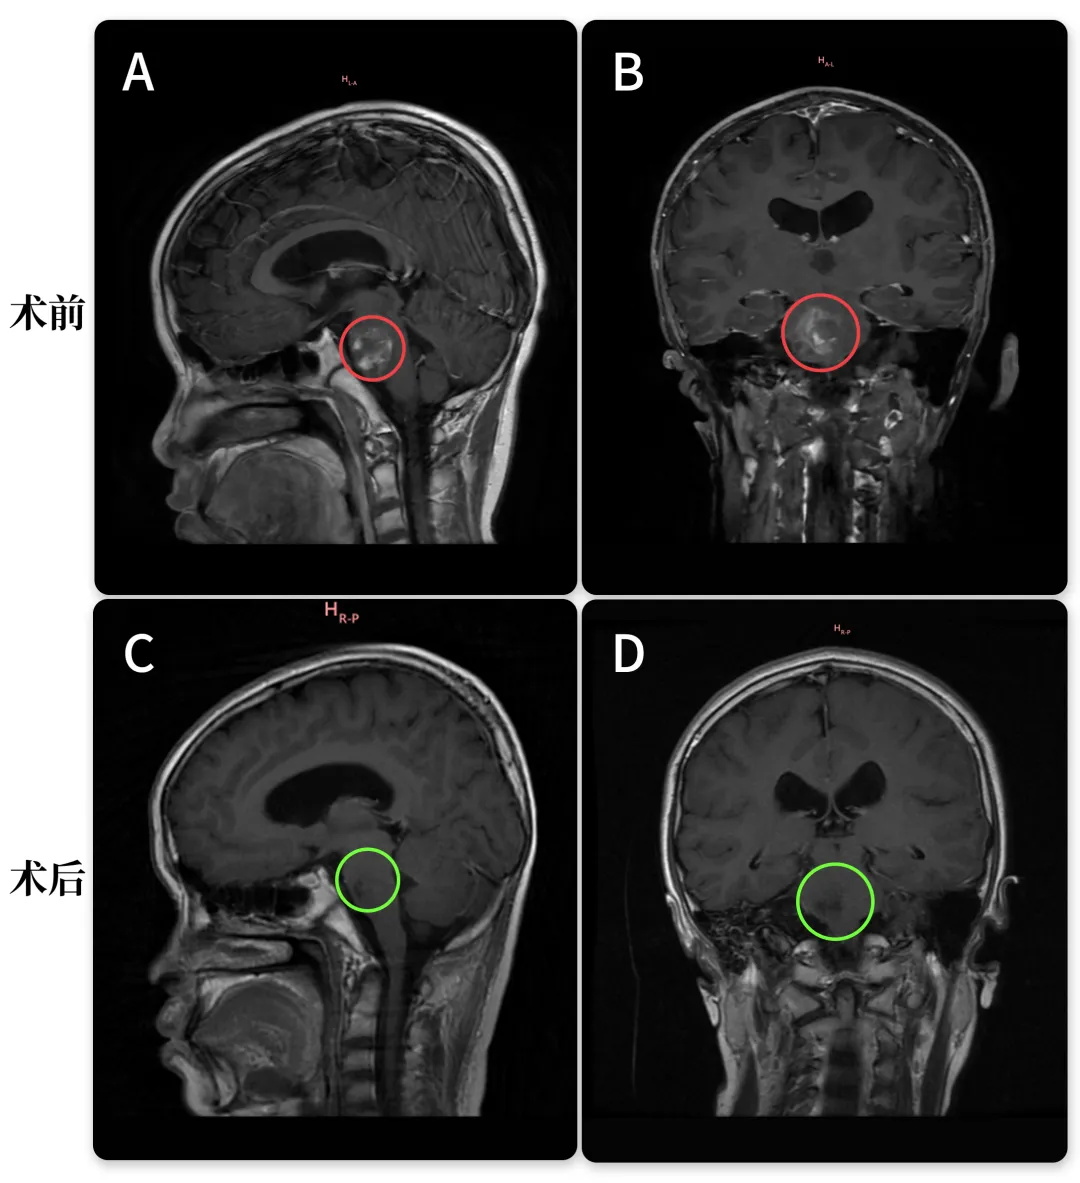

术前:脑桥占位。双眼斜视、畏光,面瘫,频发不自主扭头动作,走路稍有不稳。头颅MR(红色区域)显示:脑桥血肿,可见16 x 22 x 21mm肿块,四脑室受压变窄。

术后:头颅MR(蓝色区域)显示小脑半球及脑干形态正常,中线结构居中,原脑桥内团块状信号消失。